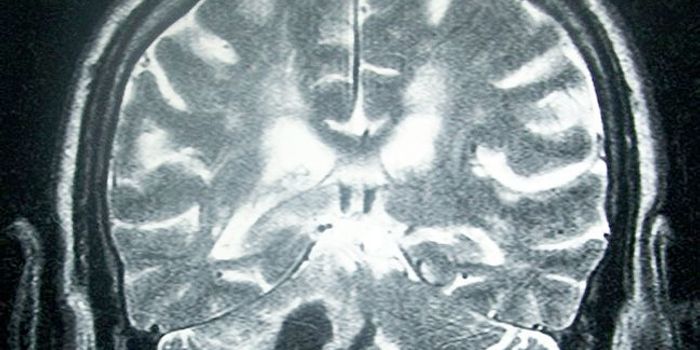

SEP 01, 2016Clinical & Molecular DXThe beloved actor Gene Wilder died earlier this week from complications of Alzheimer’s disease. He was one of the ...